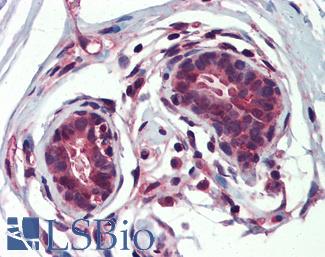

ERBB2 / HER2

Anti-ERBB2 / HER2 antibody IHC of human breast, carcinoma. Immunohistochemistry of formalin-fixed, paraffin-embedded tissue after heat-induced antigen retrieval. Antibody LS-B2133 concentration 5 ug/ml.